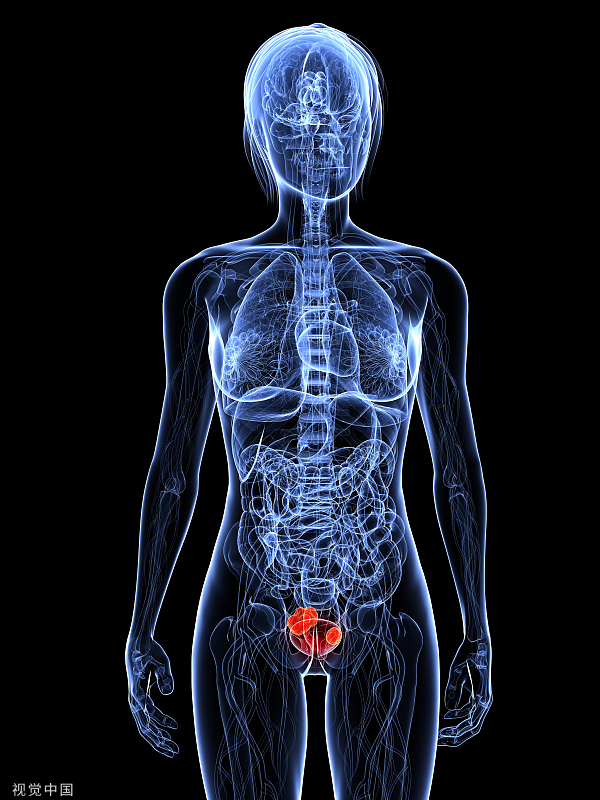

2月4日晚间,亚虹医药(688176.SH)发布了其核心产品APL-1202与化疗灌注联合使用治疗化疗灌注复发的中高危非肌层浸润性膀胱癌的关键性临床试验进展的公告。

公告显示,统计分析结果显示,尽管在部分患者人群中显示出一定的优效趋势,但是该研究未达到主要研究终点,亚虹医药决定终止APL-1202与化疗灌注联合使用在该适应症的进一步开发。

膀胱癌是全球第十大最常见的癌症,肌层浸润性膀胱癌(MIBC)约占新诊断病例的20%。公开资料显示,MIBC的推荐治疗方案是根治性膀胱切除术(RC)伴双侧盆腔淋巴结清扫术,对符合接受顺铂治疗条件的患者,在实施RC之前将先进行辅助化疗(NAC)。但大约一半的患者因存在禁忌症而无法接受顺铂治疗,有些患者则是拒绝接受化疗。目前,针对MIBC的治疗还存在许多亟待解决的挑战。

APL-1202(商品名唯施可®)是一款口服的可逆性MetAP2抑制剂,具有抗血管生成、抗肿瘤活性及调节肿瘤免疫微环境的作用。该产品有望填补膀胱癌治疗领域口服靶向药物的空白。

目前试验结果显示,APL-1202与替雷利珠单抗联合新辅助治疗肌层浸润性膀胱癌拥有良好的治疗潜力,这一联合治疗方案有望为顺铂不耐受或拒绝接受顺铂治疗的MIBC患者提供治疗方案。

公告显示,截至2023年12月31日,APL-1202与化疗灌注联合使用治疗化疗灌注复发的中高危NMIBC的关键性临床试验累计投入超过1.2亿。按照相关会计准则和公司会计政策,上述研发费用发生时已计入相应会计期间损益,不会对公司当期业绩产生重大影响。